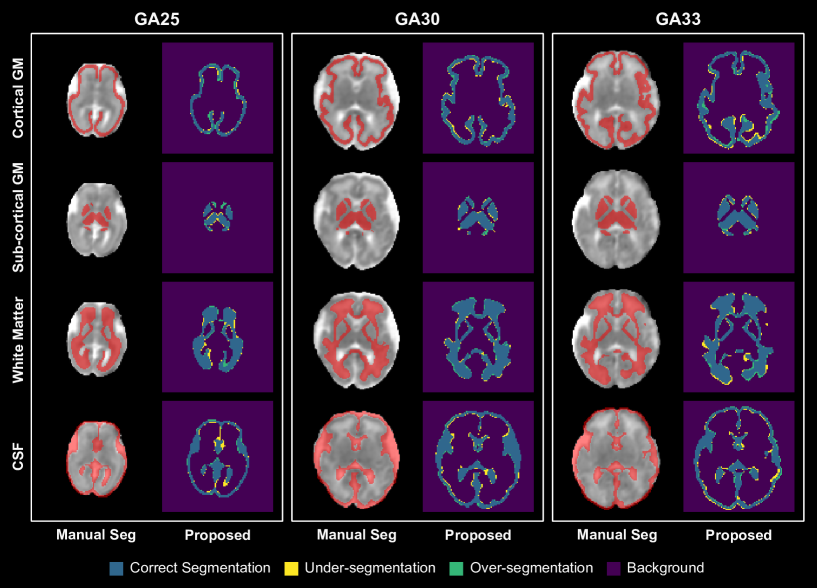

Figure 5 shows example fetal brain tissue segmentation results computed by the deep learning method compared with the manually-generated ground truth. They show that the automatic method can accurately segment all four tissue types. Visual assessments by an expert confirmed that the computed segmentations were free of any major errors. Table 1 presents quantitative segmentation performance metrics for the four tissue types. The average DSC for white matter, cortical gray matter, sub-cortical gray matter, and CSF was, respectively, 0.898, 0.830, 0.837, and 0.841. These values are in the range of performance metrics reported for the state-of-the-art segmentation methods applied on fetal T2 MRI in recently-published studies [74, 73, 71, 72]. For white matter, for example, the DSC values achieved by several deep learning methods in a recent study [74] were in the range 0.85-0.90, while for our method in this work it was 0.898±0.024plus-or-minus0.8980.0240.898\pm 0.024. Similarly, surface distance error quantified in terms of HD95 and ASSD are comparable with the results of recent deep learning methods for T2 segmentation [74], including our own work [75]. These results indicate that the proposed method is able to segment the fetal brain tissue with satisfactory accuracy in dMRI, which has an inherently lower signal quality than T2.

Refer to caption

Figure 5: Examples of segmentations predicted by our proposed method in three subjects at three different gestational ages (GA). Each panel shows the manual segmentation and the segmentation computed by the proposed method for four tissue types used in the five-tissue-type image. Please note that the last tissue type, reserved for pathological tissue [62], is omitted from this figure and excluded from this study, as it is absent in our cohort of healthy fetuses. GM stands for gray matter, and CSF stands for corticospinal fluid.